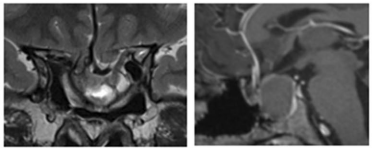

8年后,小葵出現(xiàn)漸進(jìn)性視力喪失、上瞼下垂,且突發(fā)中風(fēng)住院,檢查發(fā)現(xiàn)腫瘤復(fù)發(fā),再次進(jìn)行了手術(shù)。然而這次手術(shù)還是出現(xiàn)殘留。4個(gè)月后,患者因視力持續(xù)受損而轉(zhuǎn)至神經(jīng)外科。MRI顯示腫瘤殘余,繼發(fā)性空蝶鞍綜合征伴有鞍區(qū)前交通動(dòng)脈復(fù)合體的下移位(圖2)。繼發(fā)性空蝶鞍綜合征伴系因鞍隔缺損或垂體萎縮,蛛網(wǎng)膜下腔在腦脊液壓力沖擊下突入鞍內(nèi),致蝶鞍擴(kuò)大,垂體受壓而產(chǎn)生的一系列臨床表現(xiàn),如蝶鞍擴(kuò)大,視力減退、視野缺損等表現(xiàn)。

圖2:術(shù)前MRI顯示二次手術(shù)后腫瘤殘余、患者出現(xiàn)繼發(fā)性空蝶鞍綜合征的影像學(xué)特征